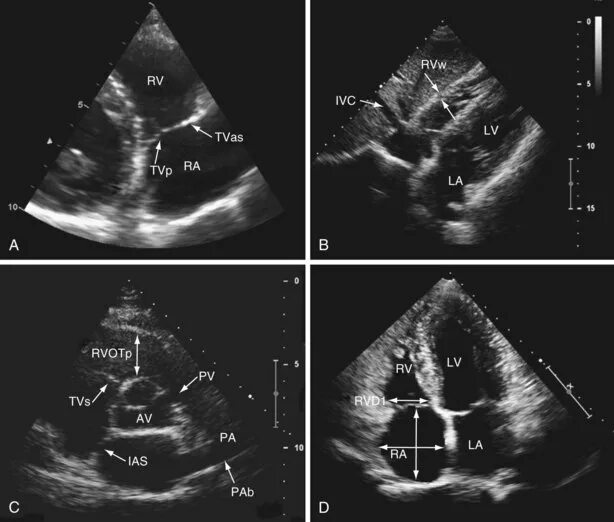

Эхокг сдла